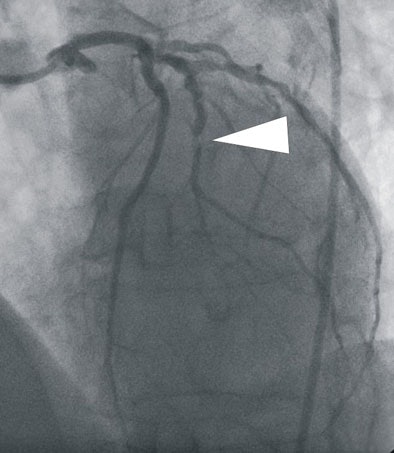

| In a 64-year-old man presenting with chest pain, 3D and multiplanar reconstructions of coronary CTA images show a significant stenosis in the first diagonal branch of the left anterior descending (LAD) artery and a 70% stenosis in the mid right circumflex artery (RCA) (arrows). All images courtesy of Dr. Balázs Ruzsics, Ph.D., and Dr. U. Joseph Schoepf. |

![]() |

| In a 64-year-old man with chest pain, conventional catheter angiography confirmed the coronary CTA findings, and described a 50% ostial stenosis with diffuse disease throughout the vessel and a discrete 90% stenosis in the mid right circumflex artery (RCA) (arrows). |